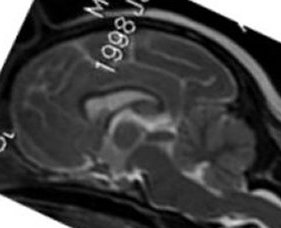

Above is a normal MRI image of a Dalmation

Red circle is normal-sized ventricle in the brain--no

hydrocephalus (fluid in ventricle)

Yellow is normal-sized cerebellum--no squashing or pinching

Green is the beginning of the spinal cord

Extension to the left of the spinal cord is the brain

stem/medulla